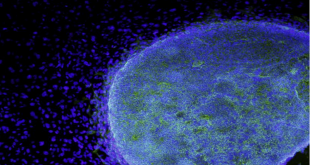

اكتشاف طريقة جديدة لعلاج السرطان

نجح الباحثون في إنشاء غدة التوتة الاصطناعية القادرة على قتل مسببات الأمراض المسؤولة عن نمو الأورام السرطانية. وقال العلماء في مركز إيلي وإديث لبحوث الخلايا الجذعية والطب التجديدي في جامعة كاليفورنيا، إن أبحاث الخلايا الجذعية المتقدمة يمكن أن تمهد يوما ما الطريق نحو إيجاد علاج للسرطان. وأوضح الباحثون أن جهازهم ...